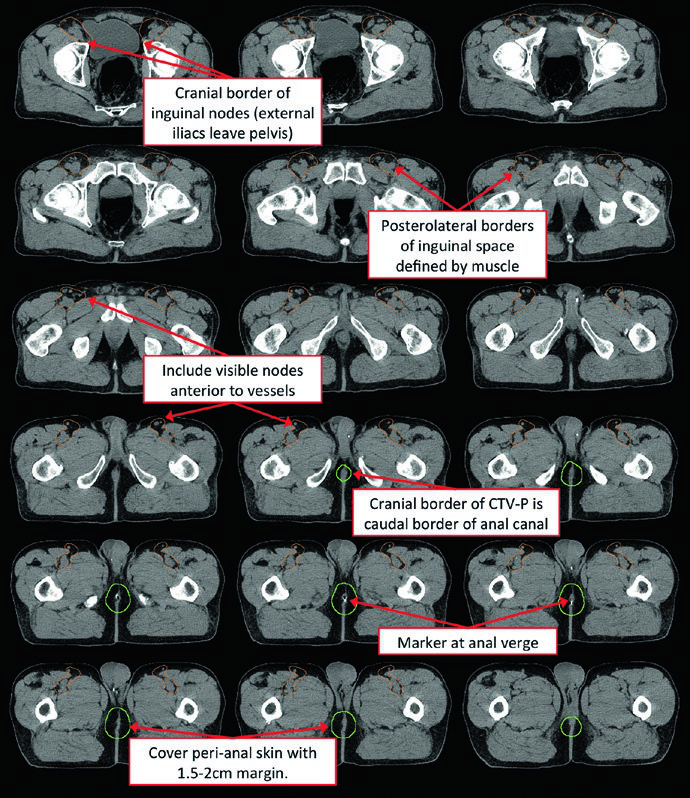

The patient should be simulated supine with arms on chest in a body mold. Prone positioning with a belly board can displace bowel anteriorly, but it is less reproducible and complicates bolus placement. A radiopaque marker should be placed at the anal verge.

Contouring Atlas: Elective Nodal Regions

The RTOG anorectal contouring atlas describes three CTV regions that should be included for all patients with anal canal cancer. The Australasian GI Trials Group Atlas details seven elective regions. There is disagreement among the RTOG, AGITG, and BNG guidelines regarding inguinal lymph node contouring — recent data show that 10–29% of involved inguinal nodes fall outside the recommended nodal borders.

| CTV-A (perirectal, presacral, internal iliac) | Lower pelvis: inferior border 2 cm below gross disease, including entire mesorectum. Mid pelvis: rectum, mesorectum, internal iliac nodes, 1 cm margin into bladder. Upper pelvis: to the bifurcation of common iliac vessels (~sacral promontory). 7–8 mm margin around internal iliac vessels |

| CTV-B (external iliac) | Border between inguinal and external iliac at the inferior extent of the internal obturator vessels (upper edge of superior pubic rami). 7–8 mm margin, at least 1 cm anteriorly |

| CTV-C (inguinal) | Inferior extent 2 cm below the saphenous/femoral junction. Entire inguinal compartment contoured including small vessels and lymph nodes |

To adequately cover the inguinal chain, the recommended approach includes: a 2 cm radial margin around the femoral vessels, 1 cm radial margin around the saphenous/femoral junction, and 3 cm medial/lateral margin along the lower inguinal ligament. The caudal border of the inguinal CTV should be at the level of the anal margin.